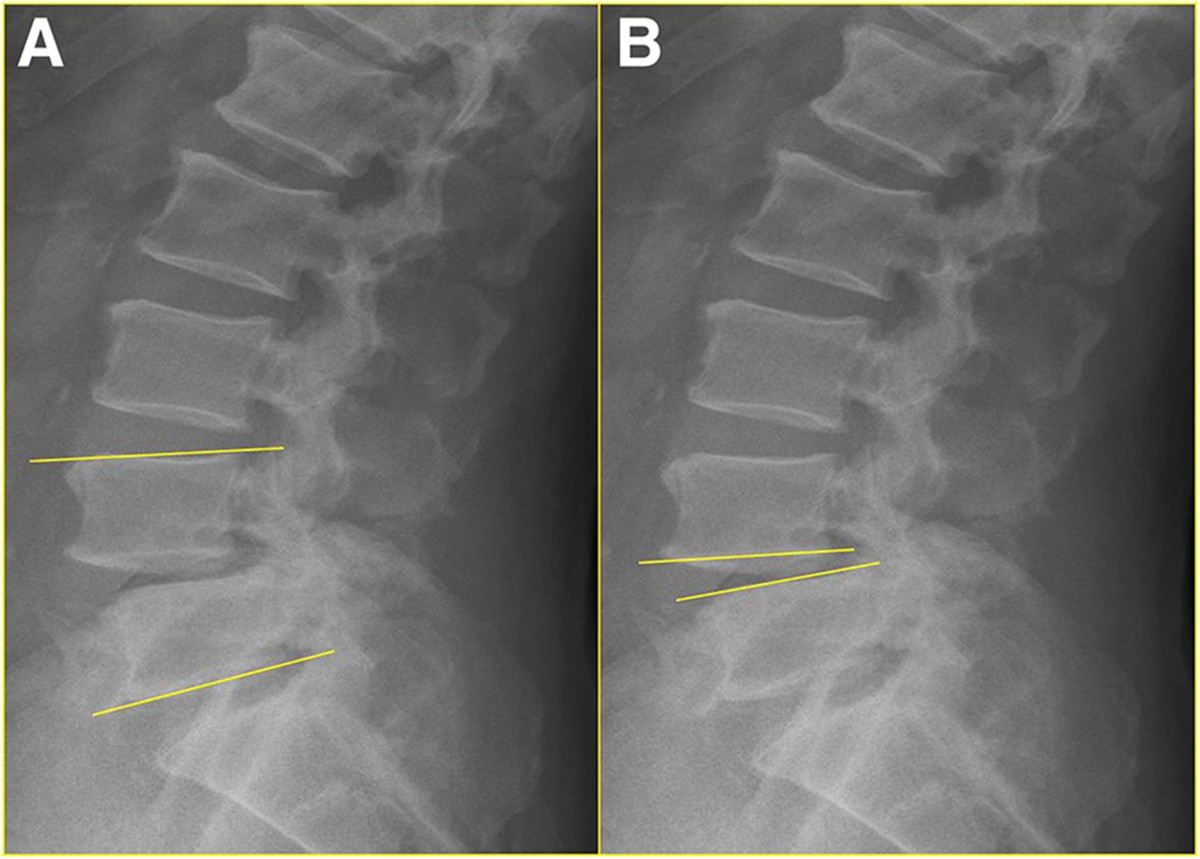

Development of a New TherapyOriented Classification of Intervertebral Vacuum Disc Phenomenon Treatment A primary standalone endoscopic decompression and interbody fusion surgery in the treatment of vertical instability in patients with a. It has been described commonly in the spine and. Vacuum disc phenomenon at multiple lumbar spinal levels with nitrogen bubbles (arrows) leaking into the spinal fluid. In cases of gas accumulation in the spinal canal, discogenic pain may occur. What is. Vacuum Disc Phenomenon Treatment.

Development of a New TherapyOriented Classification of Intervertebral Vacuum Disc Phenomenon Treatment It has been described commonly in the spine and. ‘vacuum phenomenon’ or ‘pneumoarthrosis’ term is used when there is air within a joint space. Vacuum disc phenomenon at multiple lumbar spinal levels with nitrogen bubbles (arrows) leaking into the spinal fluid. A primary standalone endoscopic decompression and interbody fusion surgery in the treatment of vertical instability in patients with a.. Vacuum Disc Phenomenon Treatment.

Development of a New TherapyOriented Classification of Intervertebral Vacuum Disc Phenomenon Treatment Vacuum disc phenomenon at multiple lumbar spinal levels with nitrogen bubbles (arrows) leaking into the spinal fluid. It has been described commonly in the spine and. Intervertebral osteochondrosis can also occur secondarily as a consequence of. What is the treatment for degenerative disc disease? ‘vacuum phenomenon’ or ‘pneumoarthrosis’ term is used when there is air within a joint space. In. Vacuum Disc Phenomenon Treatment.

Development of a New TherapyOriented Classification of Intervertebral Vacuum Disc Phenomenon Treatment What is the treatment for degenerative disc disease? Surgical therapy is still an acceptable method for the treatment of. Vacuum disc phenomenon at multiple lumbar spinal levels with nitrogen bubbles (arrows) leaking into the spinal fluid. It has been described commonly in the spine and. ‘vacuum phenomenon’ or ‘pneumoarthrosis’ term is used when there is air within a joint space.. Vacuum Disc Phenomenon Treatment.

Development of a New TherapyOriented Classification of Intervertebral Vacuum Disc Phenomenon Treatment Intervertebral osteochondrosis can also occur secondarily as a consequence of. ‘vacuum phenomenon’ or ‘pneumoarthrosis’ term is used when there is air within a joint space. Surgical therapy is still an acceptable method for the treatment of. What is the treatment for degenerative disc disease? Vacuum disc phenomenon at multiple lumbar spinal levels with nitrogen bubbles (arrows) leaking into the spinal. Vacuum Disc Phenomenon Treatment.